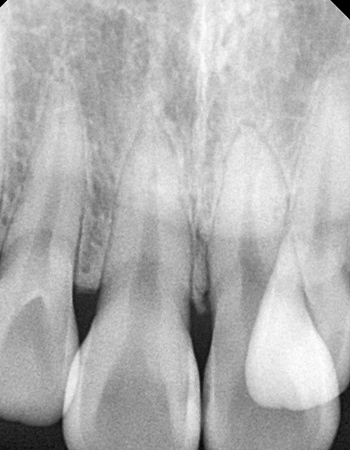

Evaluation of miniscrew-assisted rapid palatal expansion success by comparing width of circummaxillary sutures before expansion in adult male patients” – Angle Orthodontics

논문 발췌 사진

이지민 원장은 성인 비발치 교정의 핵심인 비수술 악궁 확장 가능성을, 직접 연구한 논문 결과를 바탕으로 사전에 정밀 분석·예측합니다.

이 연구들은 현재 연세꿈꾸는치과의

교정 프로토콜에 적용되고 있습니다.